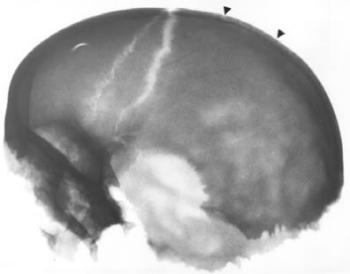

A poroticus hyperostosis (szinonimák: cribra orbitalia, cribra cranii, hyperostosis spongiosa, hyperostosis porotica, osteoporosis cranii) elsősorban a koponya, (főként a szemüreg) elváltozása (122. ábra) ám megjelenhet valamennyi lapos és csöves csonton. Mikroszkópos képével Hamperl és Weiss (1955), Marcsik és Kósa (1976), az elektronmikroszkópos és hisztomorfometriai eltérésekkel Józsa és Pap (1991) foglalkoztak. Morfológiai képe a folyamat súlyossága szerint eltérő. A poroticus típusban a corticalison tág nyílások keletkeznek (123. ábra), a spongiosus alakban a corticalis felszivódik, a felületet szívacsos állomány képezi (124. ábra), trabeculáris formában a diploe gerendái a környező csont szintje fölé burjánzanak (125. ábra) ami a rtg-felvételen „kefekoponya” alakjában jelentkezik (126. ábra). Mikroszkóposan a spongiosa gerendáinak feldúsulása, a gerendákon másodlagos üregek kialakulása állapítható meg (Józsa és Pap 1991), az egységnyi ürtartalomban megnő a csontvelőt hordozó felület, az újonnan képződő gerendák kóros szerkezetüek (123. ábra, 124. ábra, 125. ábra). Fokozott vörösvértest produkcióval járó valamennyi kórképben megjelenhet, vashiányos vérszegénységben 60-90%, Cooley anemiában 100%, sarlósejtes anaemiában 50-60%, maláriásokon 40-60%, cyanoticus szívfejlődési rendellenességekben 1-5% gyakoriságú (15. táblázat).

126. ábra. A koponya rtg-képén látható „kefeszerű” rajzolatot (nyíl) a lamina externa szintje fölé növekvő trabeculák idézik elő. 9–11. század, 2-4 éves gyermek